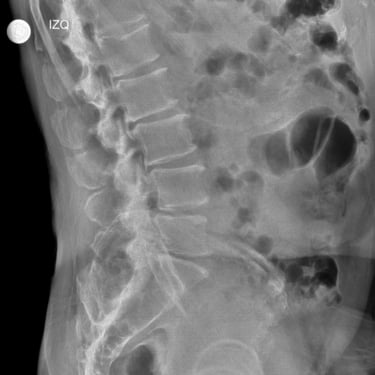

La listesis L4–L5 asociada a estenosis lumbar severa se caracteriza por el deslizamiento vertebral y el estrechamiento del canal espinal, generando dolor lumbar, claudicación neurogénica y compromiso radicular. Cuando el tratamiento conservador no logra un control adecuado de los síntomas, la fijación transpedicular (FTP) asociada a la fusión intersomática transforaminal (TLIF) constituye una alternativa quirúrgica eficaz. Este procedimiento permite descomprimir las estructuras nerviosas, restaurar la alineación vertebral y proporcionar una estabilización sólida del segmento afectado, favoreciendo una recuperación funcional segura y una mejor calidad de vida.